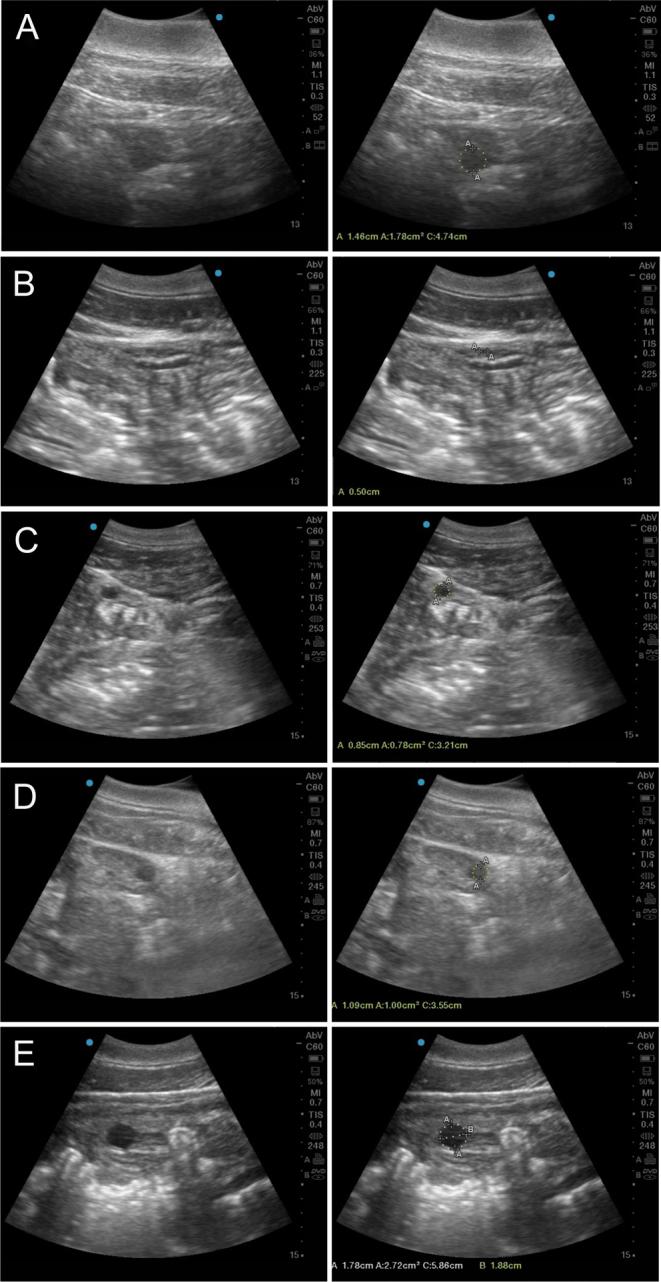

To gain more knowledge about the influence of hormone regulation on follicle development, ovarian ultrasounds were performed, and urinary hormone profiles were determined in ovulating and non-ovulating female bottlenose dolphins (n = 15) following estrus synchronization with altrenogest. Ovarian ultrasounds were conducted daily, post synchronization to describe follicular recruitment in relationship to the endocrine profile. Follicle sizes were grouped into very small (VSM), small (SM), medium (MD) and large (LG). In ovulating females, two follicular waves were identified, and follicular deviation towards establishing a dominant follicle only occurred during the second wave. For non-ovulating females, only the first wave was observed. For all urinary hormones, the non-ovulating group presented significantly lower concentrations of follicle stimulating hormone (uFSH), luteinizing hormone (uLH), estrone conjugates (uE1-C) and estriol (uE3) but similar progestagen and cortisol concentrations compared to the ovulating group. Concentrations of uE1-C and uE3 and numbers of MD and LG follicles significantly (P < 0.05) increased, while uFSH concentrations significantly (P < 0.05) decreased as ovulation approached. Urinary LH significantly increased concurrently with increasing numbers of LG follicles and decreasing numbers of SM follicles. The characterization of follicular development and its relationship with hormone assessments complements our understanding of follicular recruitment post-synchronization in bottlenose dolphins and provides new information concerning differences between ovulating and non-ovulating females in response to an estrous synchronization protocol.

为了更深入了解激素调节对卵泡发育的影响,我们对15只雌性宽吻海豚进行了卵巢超声检查,并在使用烯丙孕素进行发情同步后,测定了排卵和不排卵雌性海豚的尿激素谱。同步发情后每天进行卵巢超声检查,以描述卵泡募集与内分泌谱之间的关系。卵泡大小分为极小(VSM)、小(SM)、中(MD)和大(LG)。在排卵雌性海豚中,识别出两个卵泡波,且仅在第二个卵泡波期间出现向优势卵泡发展的卵泡偏离。对于不排卵雌性海豚,仅观察到第一个卵泡波。与排卵组相比,所有尿激素中,不排卵组的促卵泡激素(uFSH)、促黄体生成素(uLH)、雌酮结合物(uE1-C)和雌三醇(uE3)浓度显著较低,但孕激素和皮质醇浓度相似。随着排卵临近,uE1-C和uE3浓度以及MD和LG卵泡数量显著(P < 0.05)增加,而uFSH浓度显著(P < 0.05)降低。尿LH随着LG卵泡数量增加和SM卵泡数量减少而显著增加。卵泡发育的特征及其与激素评估的关系补充了我们对宽吻海豚同步发情后卵泡募集的理解,并提供了有关排卵和不排卵雌性海豚对发情同步方案反应差异的新信息。